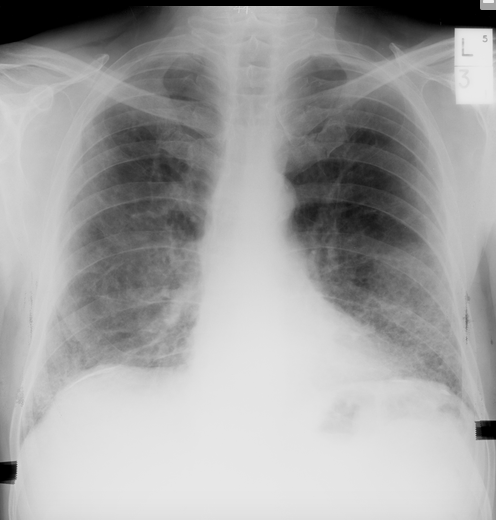

R) heart failure